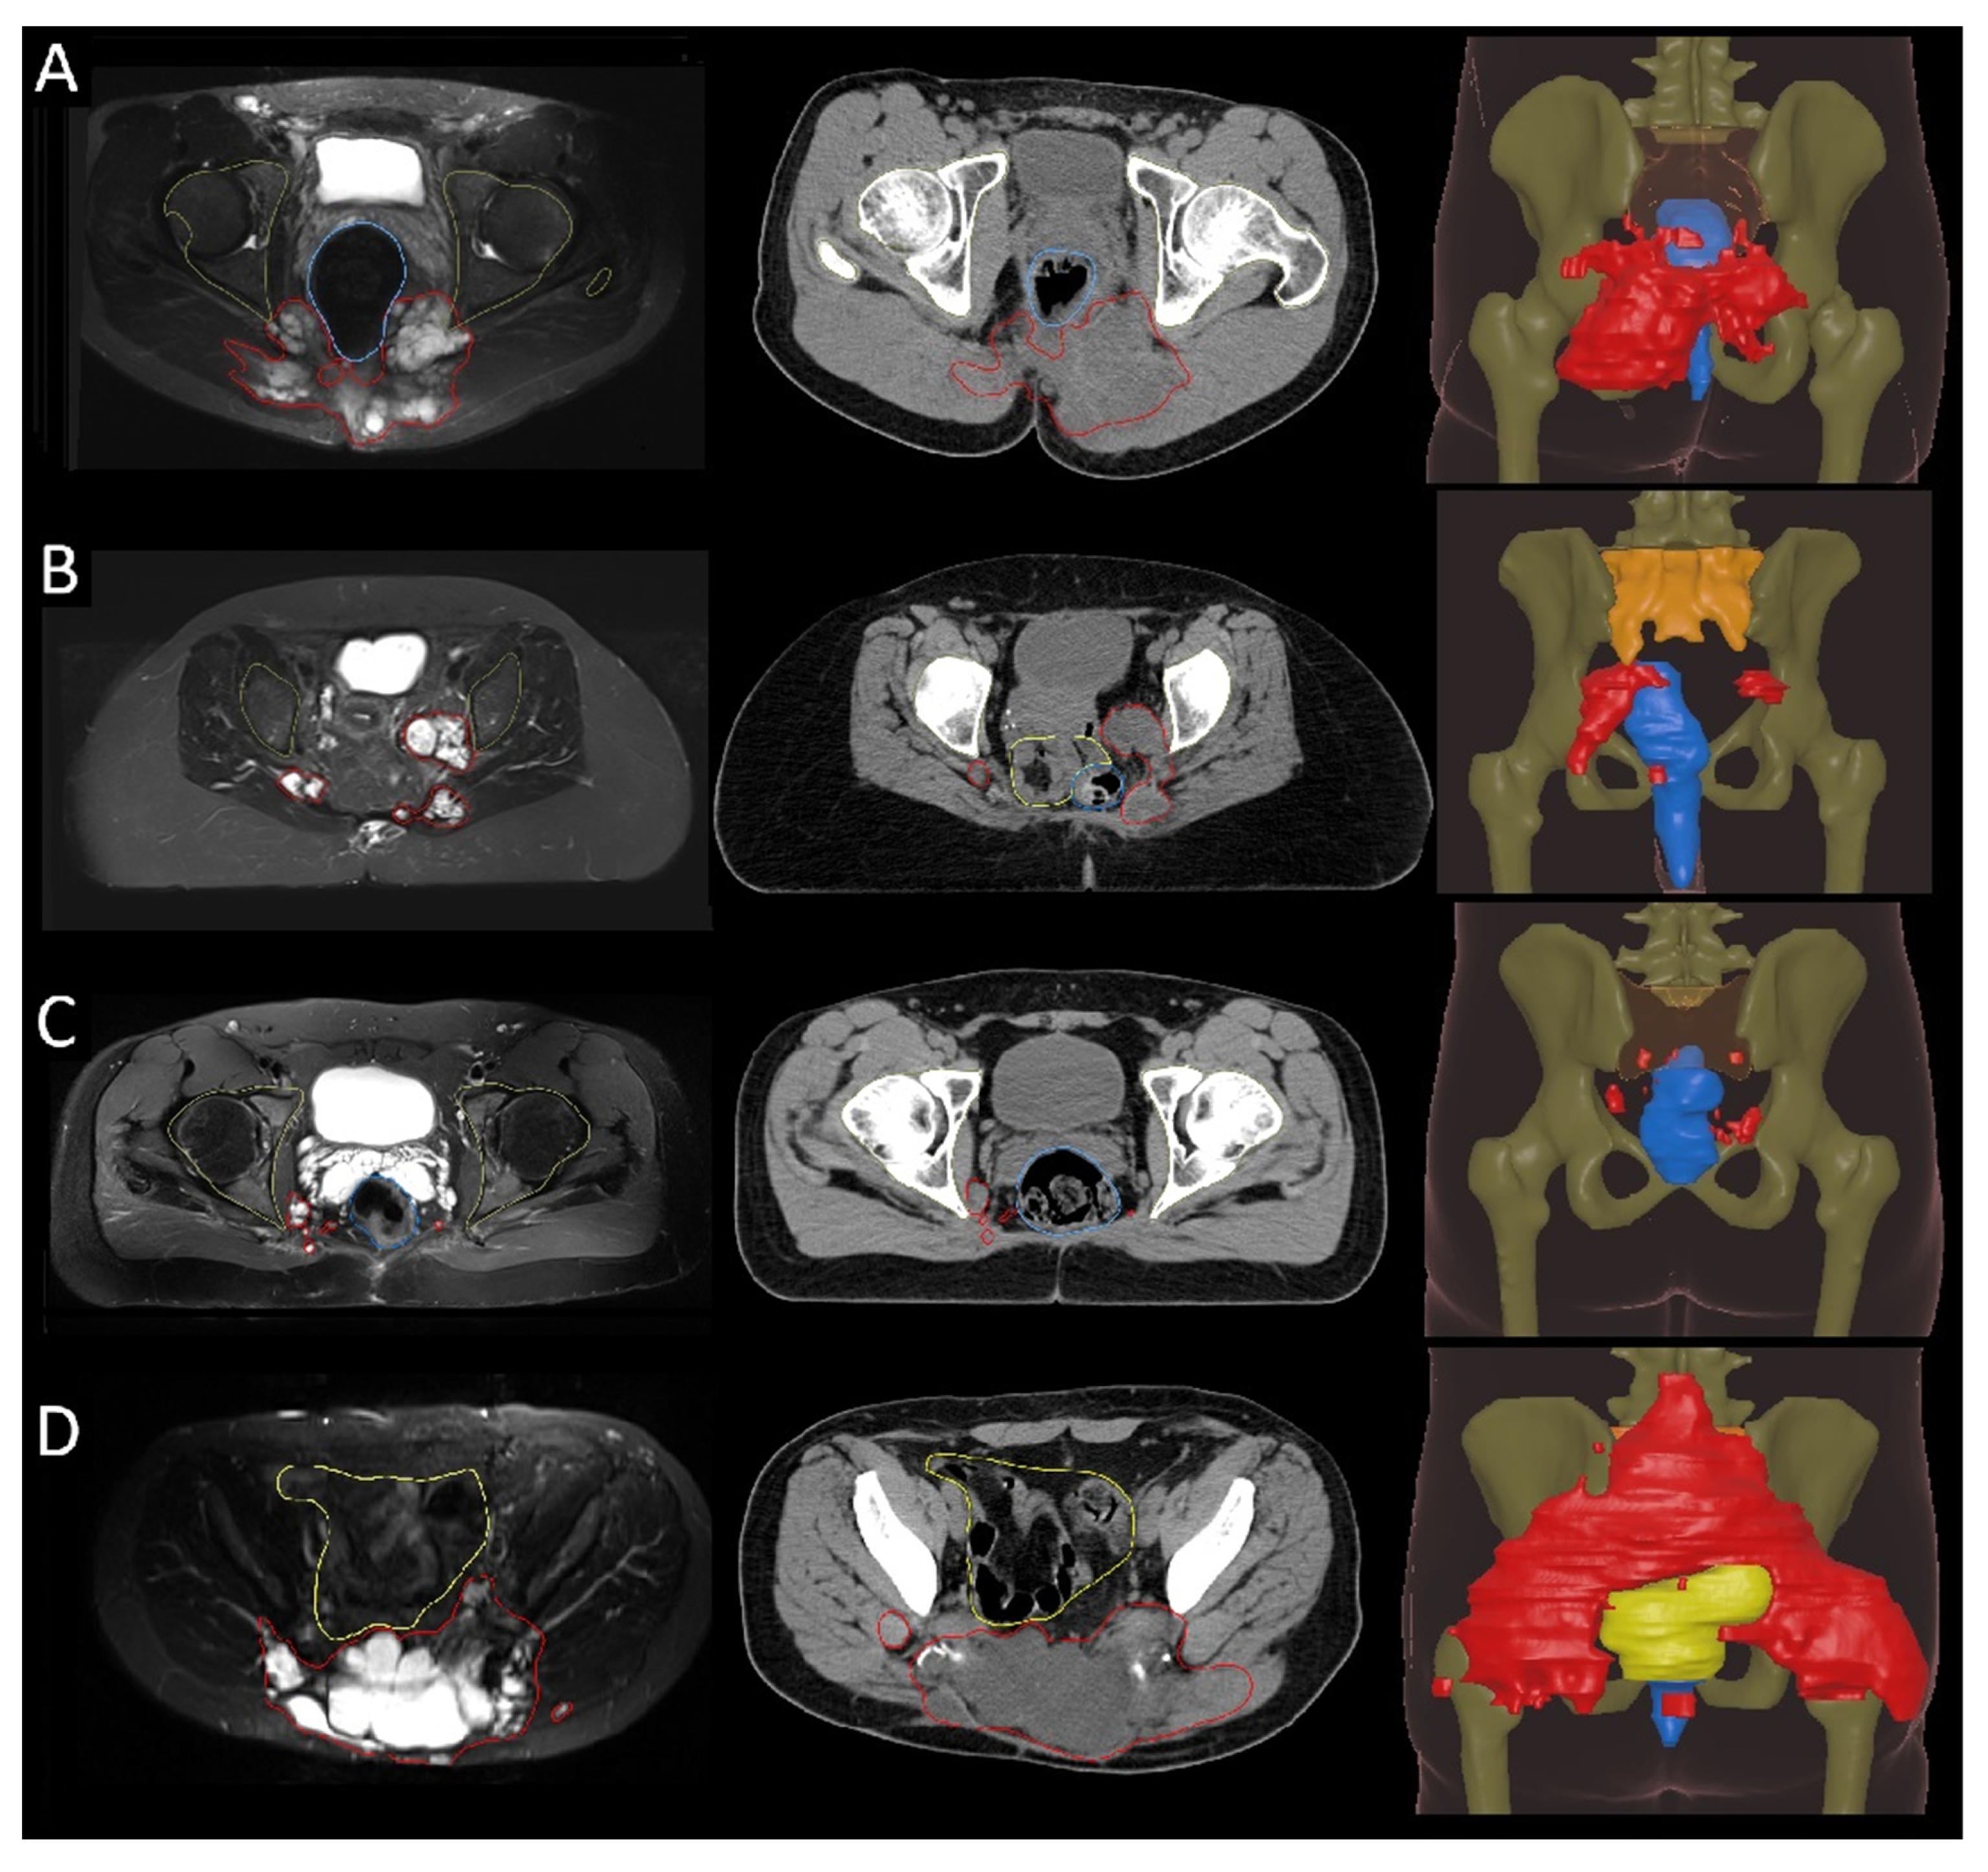

3.2. Recurrence Patterns

3.3. Postoperative Radiotherapy Planning Based on Recurrence Patterns